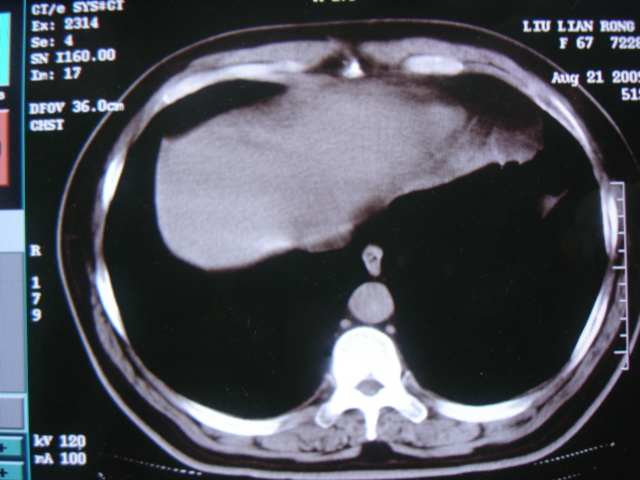

第三次ct2009.8.21